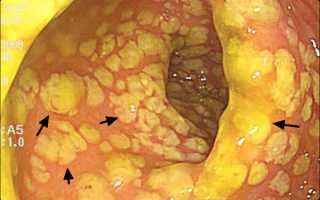

Для диагностики псевдомембранозного колита в первую очередь используют определение в кале энтеротоксина А количественным и качественным методом (антигенный тест), а также цитотоксина В. Если нет возможности для использования этих методов, то проводят КТ, рентгенодиагностику кишечника. Во время исследования врач может обнаружить утолщение стенки кишечника и воспалительный выпот в брюшной полости(асцит). Важной для диагностики воспалительного процесса является колоноскопия.

Существует три стадии классификации псевдомембранозного колита:

- Катаральное воспаление – отек и гиперемия слизистой.

- Эрозивно-геморрагическое поражение.

- Псевдомембранозное изменение кишечника.

Во время колоноскопии проводится забор материала для гистологии. Это исследование позволяет определить глубину поражения слизистой кишечника, наличие некротического и язвенного повреждения.